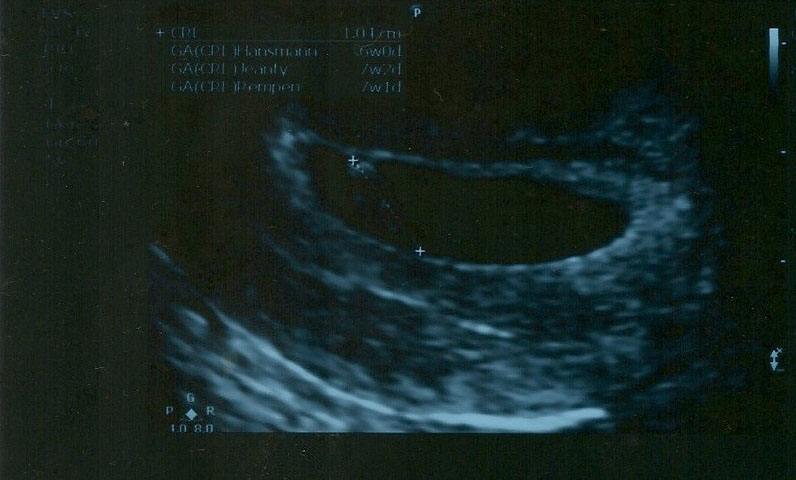

Ramzi theory: Pls guess whether a boy or girl in 7 weeks trans vaginal scan

Attachment 13219